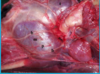

What nerve supplies the inguinal skin, prepuce, and cremaster m., some scrotum? What structures travel through the inguinal canal?

Genitofemoral n.